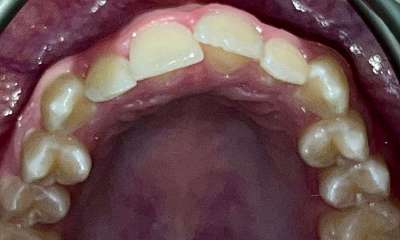

This patient presented with concerns about the damage his teeth had sustained from his bite and previous habits. His lower teeth had caused erosion and wear on the palatal surfaces and incisal edges of his upper front teeth. He was also concerned about the crowding of the lower front teeth. His primary goal was to create a more protected alignment and function of his teeth to support better oral health and longevity.

Due to a sensitive gag reflex, he first trialled nightly whitening trays for two weeks to assess whether he could tolerate aligner wear. This approach helped him proceed with ...